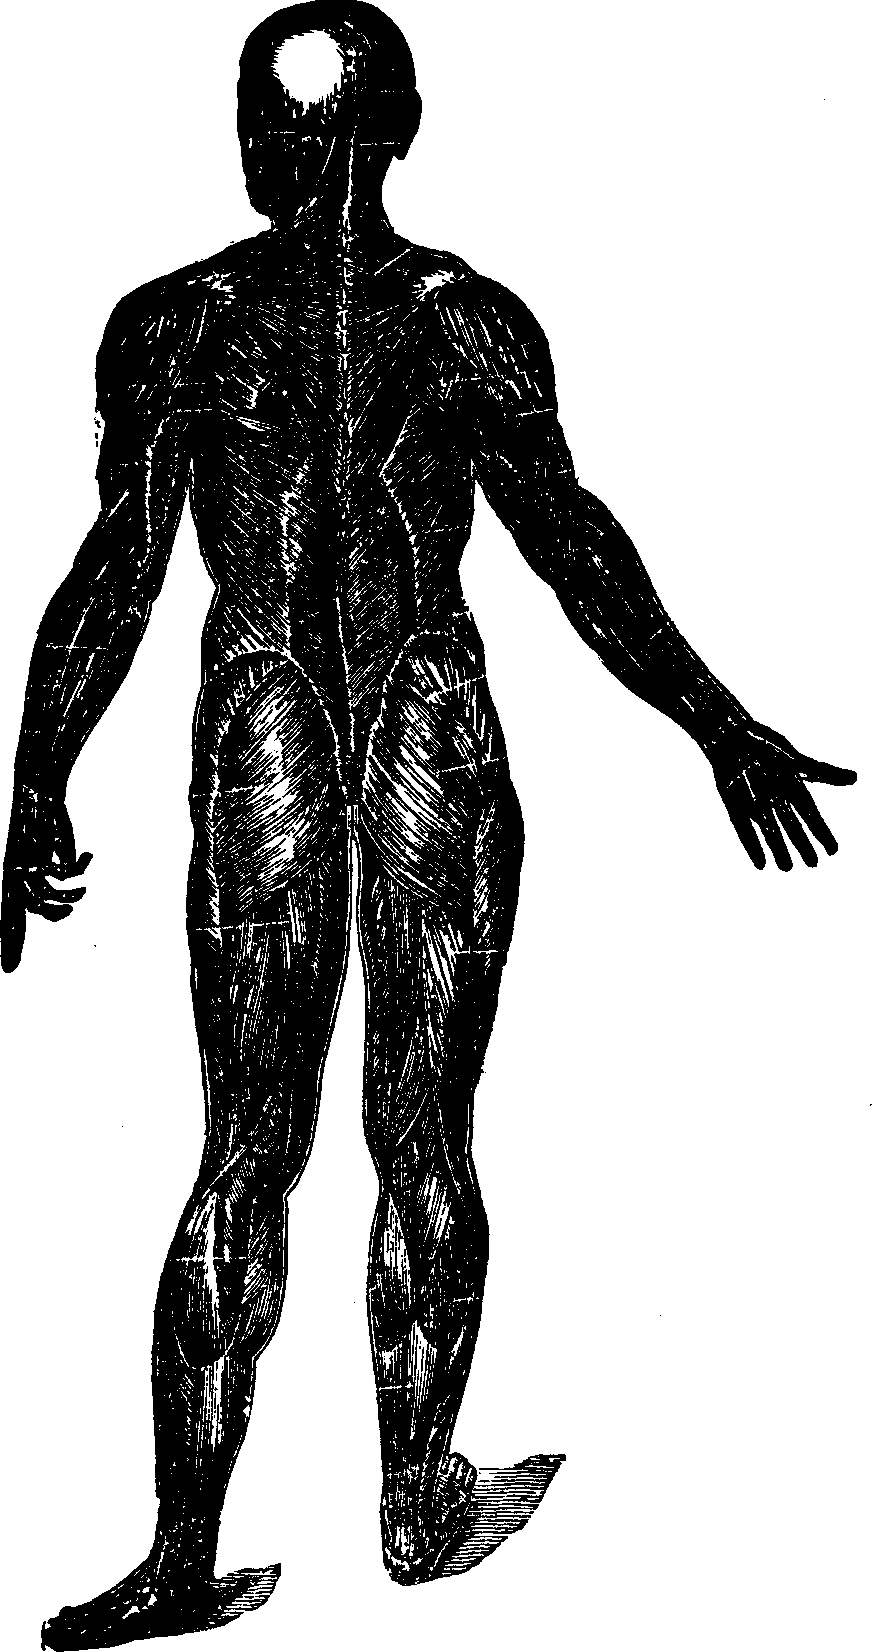

Fig.

25. A representation of the superficial layer of muscles on the posterior

portion of the body.